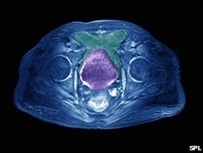

Cálculos renais, dos sintomas ao tratamento

Os cálculos podem ser desde assintomáticos até a apresentação de cólica renal, que cursa com dor intensa no flanco ou abdominal, dor ao urinar, presença de sangue na urina, urgência miccional e náuseas ou vômitos.

Quanto ao diagnóstico, geralmente é feito com exames de imagem como ultrassonografia, tomografia computadorizada (TC) ou radiografia simples, e análise da urina para detectar a presença de sangue ou cristais.